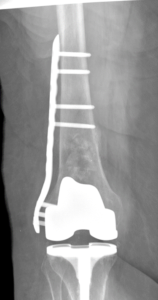

Hip, knee, and shoulder replacement including direct anterior total hip arthroplasty